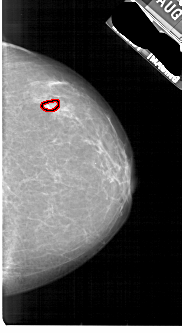

A_1891_1.RIGHT_MLO

LEFT_MLO LINES 5491 PIXELS_PER_LINE 2956 BITS_PER_PIXEL 12 RESOLUTION 43.5 NON_OVERLAY

RIGHT_MLO LINES 5491 PIXELS_PER_LINE 2746 BITS_PER_PIXEL 12 RESOLUTION 43.5 OVERLAY

FILE: A_1891_1.RIGHT_MLO.OVERLAY

TOTAL_ABNORMALITIES 1

ABNORMALITY 1

LESION_TYPE CALCIFICATION TYPE PLEOMORPHIC DISTRIBUTION CLUSTERED

ASSESSMENT 4

SUBTLETY 2

PATHOLOGY BENIGN

TOTAL_OUTLINES 1

BOUNDARY